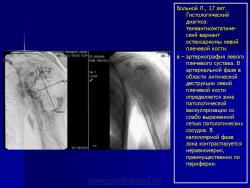

Паростальная остеосаркома - редкая (составляет около 3-4% всех остеосарком) медленно растущая костеобразующая поверхностная (растет на поверхности периоста) высокодифференцированная опухоль. При рентгенологическом исследовании большинство опухолей прикрепляется к кортикальной пластинке на протяжении 1 см или более, крупные опухоли опоясывают кость; определяются дольчатые и кальцинированные массы на метафизарной поверхности длинных костей, центральная часть опухоли более минерализована, чем периферическая, периостальная реакция отсутствует; часто выявляются, особенно при исследовании КТ, неминерализованные мягкотканные массы, расположенные вблизи минерализованного компонента. Гистологическая картина характеризуется формированием среди фибробластоподобного клеточного компонента хорошо дифференцированных афункционально расположенных костных трабекул, может содержать хрящ, в том числе в качестве хрящевого покрытия, периферическая часть опухоли более клеточная и содержит меньше кости. Часто ошибочно интерпретируется как доброкачественное реактивное поражение (посттравматический периостит, флоридный реактивный периостит, оссифицирующий миозит) и, наиболее часто, как костно-хрящевой экзостоз. Однако в последнем хрящевое покрытие не содержит злокачественных клеток, без ядерного полиморфизма и двуядерных клеток, на границе хряща и кости определяется энхондральная оссификация, отсутствует веретеноклеточный компонент, губчатая кость состоит из зрелой пластинчатой кости с жировым костным мозгом.